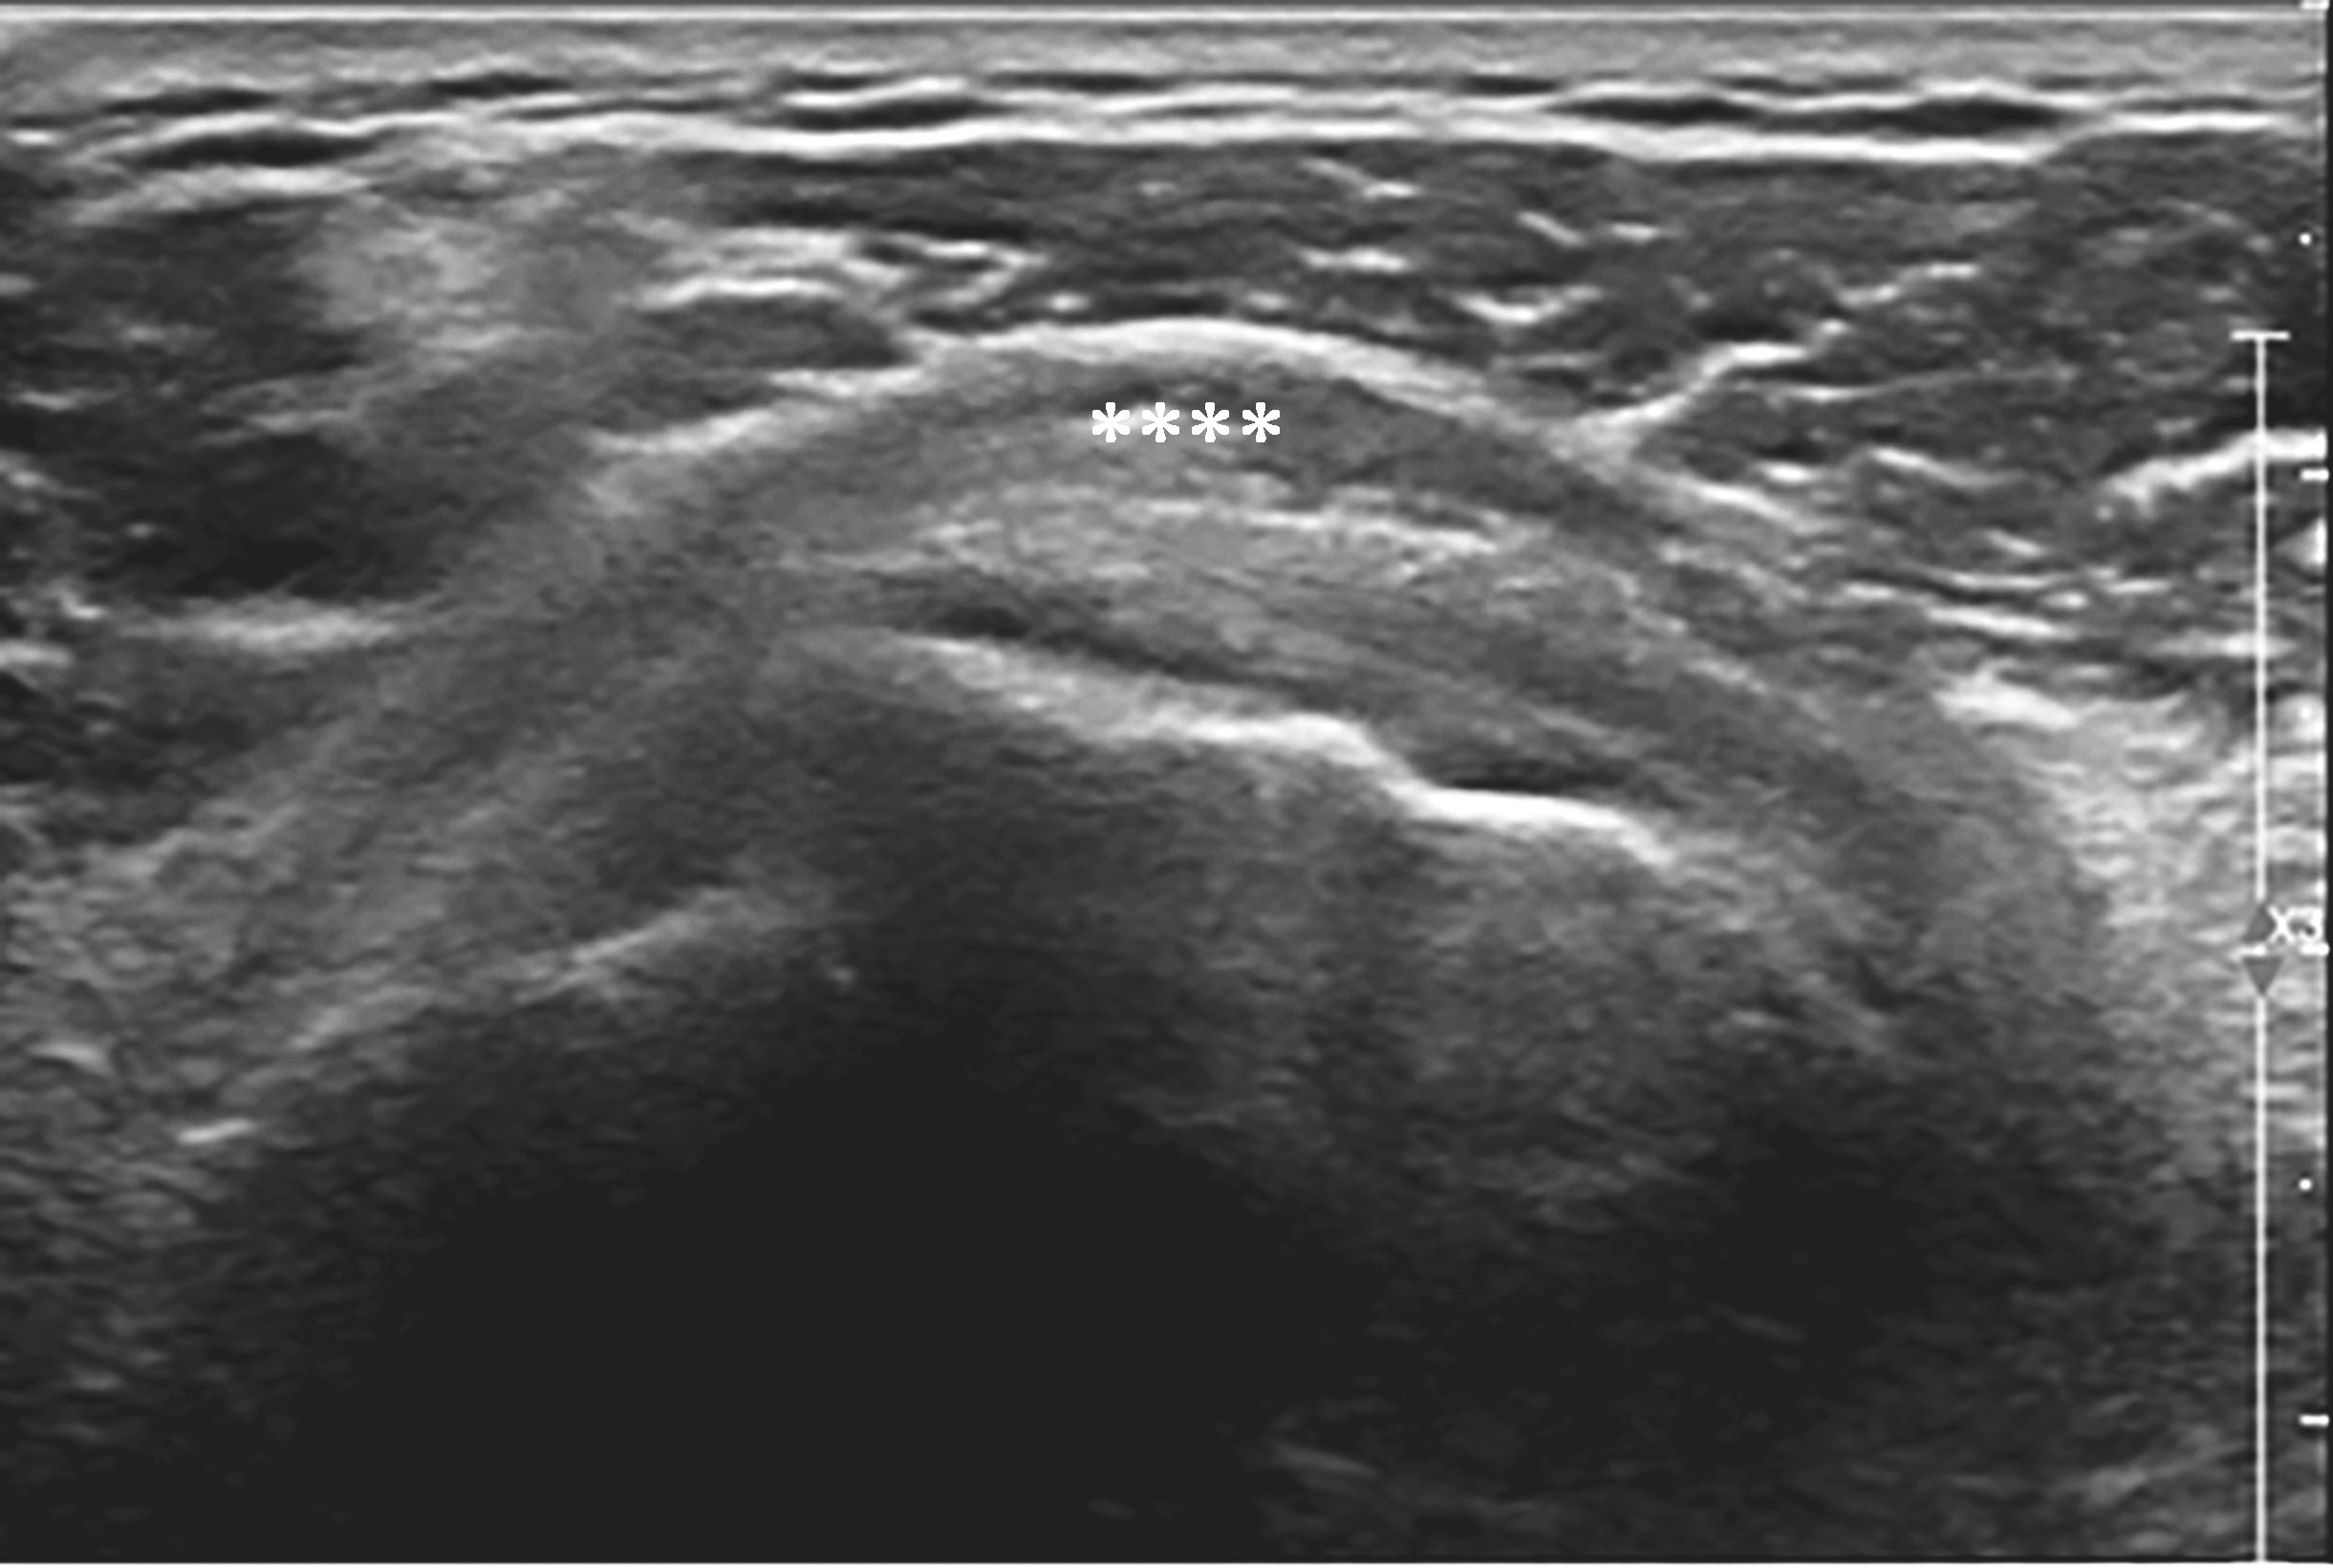

横放在肩关节前方,选择肩峰滑囊较厚或囊液较多处为靶目标(图2-1-2)。

▲ 图2-1-2 肩峰下-三角肌下滑囊炎超声图

星号:肩峰下滑囊增厚伴滑膜增生

1.正常肩峰下-三角肌下滑囊厚度<2mm,当滑囊发炎、增厚,厚度≥2mm时,内有时可见积液、滑膜增生,急性期滑膜内学流信号丰富,此刻,肩峰撞击试验往往呈阳性。